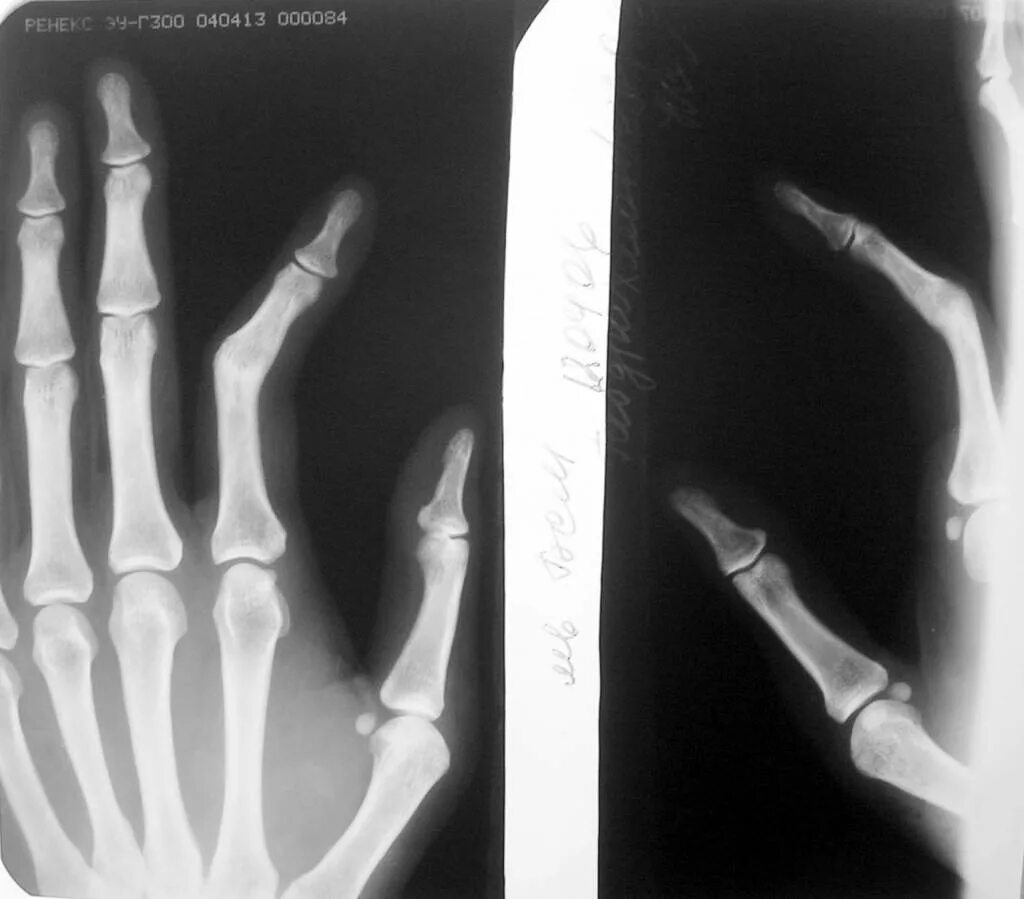

Неправильно срослась кость после перелома